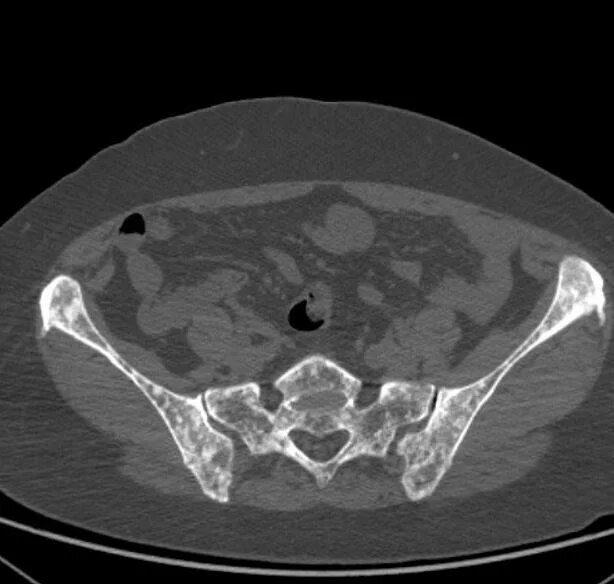

Метастазы в крестце